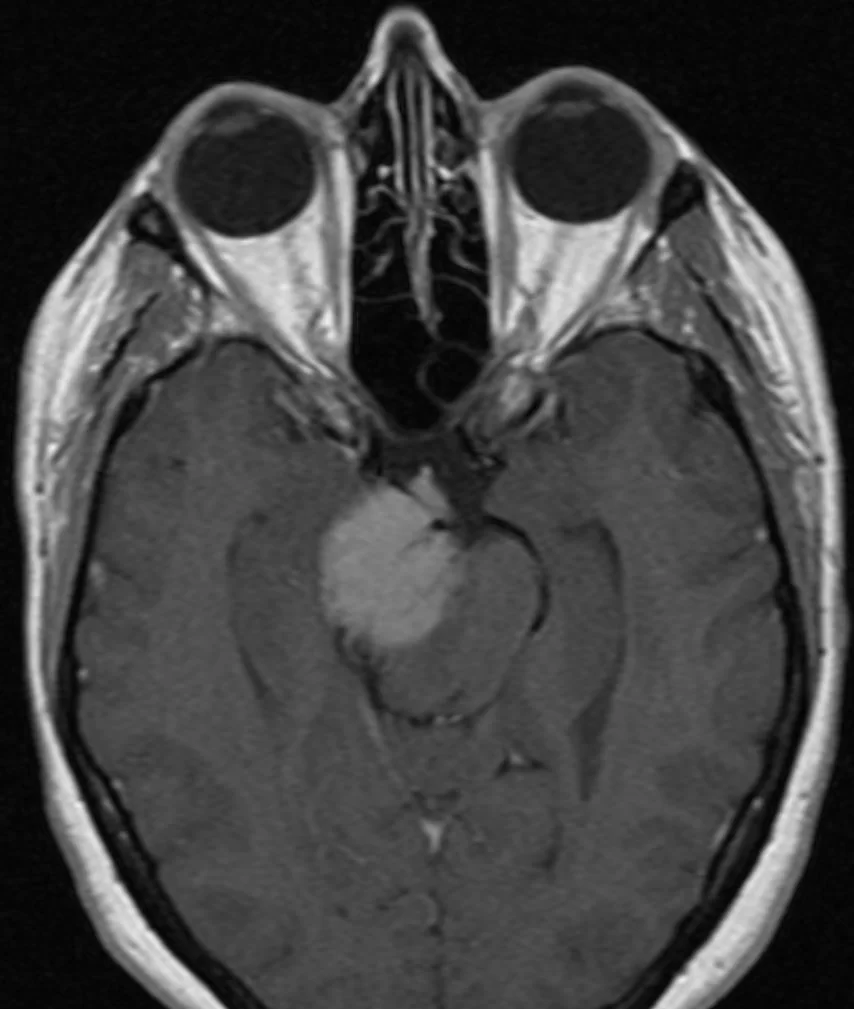

Ο απεικονιστικός έλεγχος με μαγνητική τομογραφία ανέδειξε ευμεγέθη όγκο με επέκταση τόσο στον μέσο όσο και στον οπίσθιο κρανιακό βόθρο και σημαντική πίεση επί του στελέχους, συμβατό με μηνιγγίωμα του λιθοειδούς-αποκλίματος.

Διενεργήθη συνδυασμένη υποκροτάφιος – προσιγμοειδική προσπέλαση.

Η μετεγχειρητική αξονική τομογραφία εγκεφάλου δείχνει σημαντική μείωση του όγκου, με ελάχιστα υπολειμματικά στοιχεία στην περιοχή του σηραγγώδους κόλπου δεξιά. Η ιστολογική εξέταση ανέδειξε μηνιγγίωμα (WHO I).